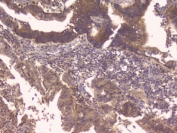

OPG antibody immunohistochemistry analysis in formalin fixed and paraffin embedded human kidney carcinoma.